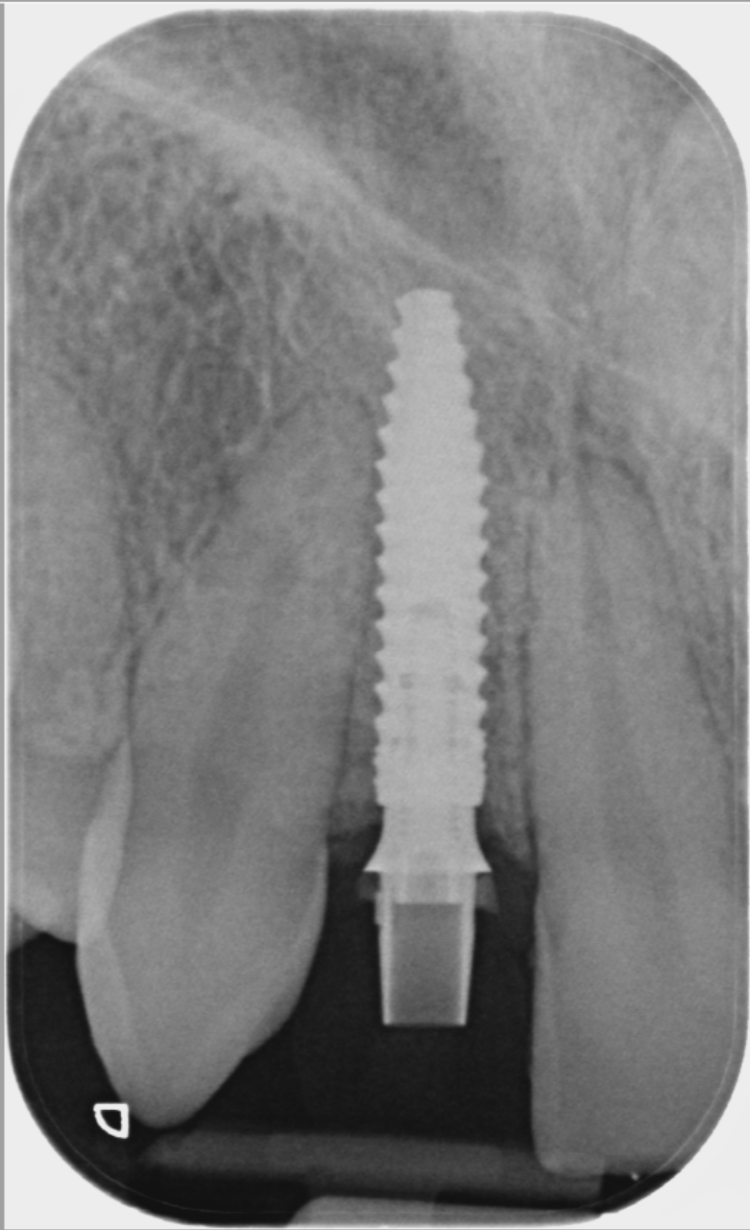

Post-surgical healing and impressions (August 2023)

A week after the surgery, the patient was seen for a healing review, during which X-rays were taken and sutures were removed. After sufficient healing, the patient returned for an impression appointment, where the temporary teeth were removed and scans were taken to fabricate the final crowns.